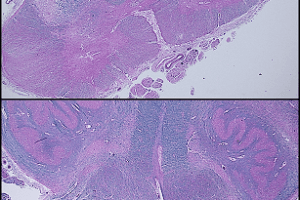

McArdle disease, H&E and PAS stain

McArdle Disease

McArdle disease is a glycogen storage disease in which the enzyme muscle myophosphorylase is deficient. It is commonly known as glycogen storage disease V. Read more »